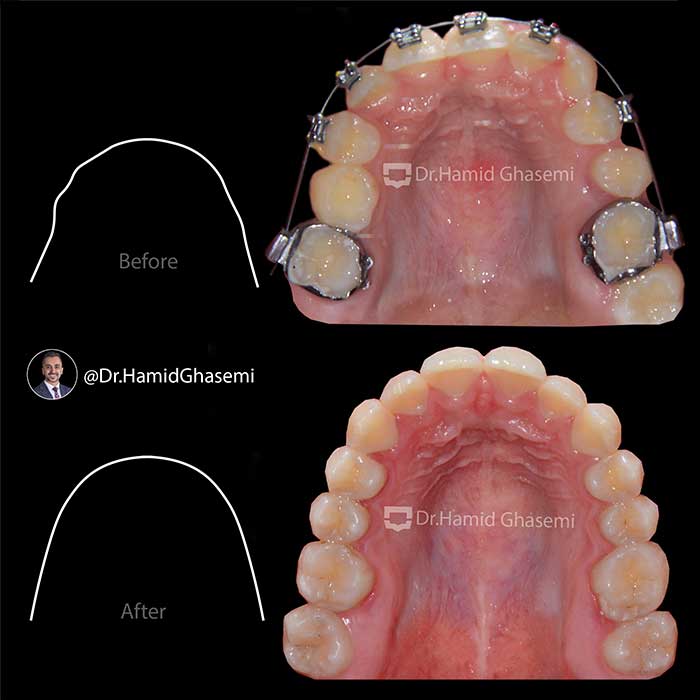

درمان ارتودنسی بدون کشیدن دندان در دختر خانم ۱۵ ساله با مشکل نهفتگی دندان نیش بالا و انحراف میدلاین دندانی در مدت ۲۲ ماه انجام شد.

Non extraction orthodontic treatment of 15 years old girl with impacted upper canine and upper dental midline deviation done within 22 months.